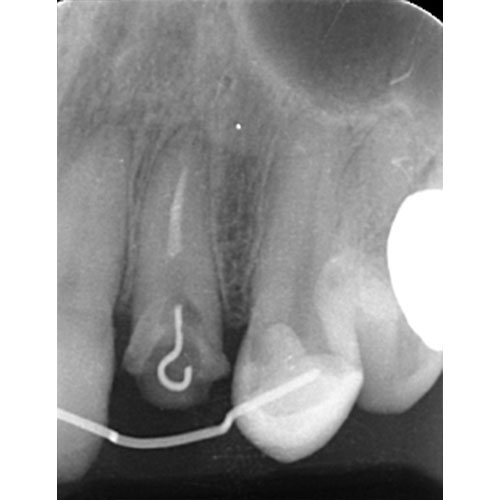

左上2は広範囲にわたってCRが充填されているのがわかります。またその周囲に透過像があり、カリエスになっていることもわかります。

| 根の中の薬が十分に充填されておらず、根の先が周りと比べて黒くなっており、炎症があると判断できます。 | 根の中にしっかりとお薬を緊密に充填しましたが、まだ根の先に黒くなっている部分があります。 |